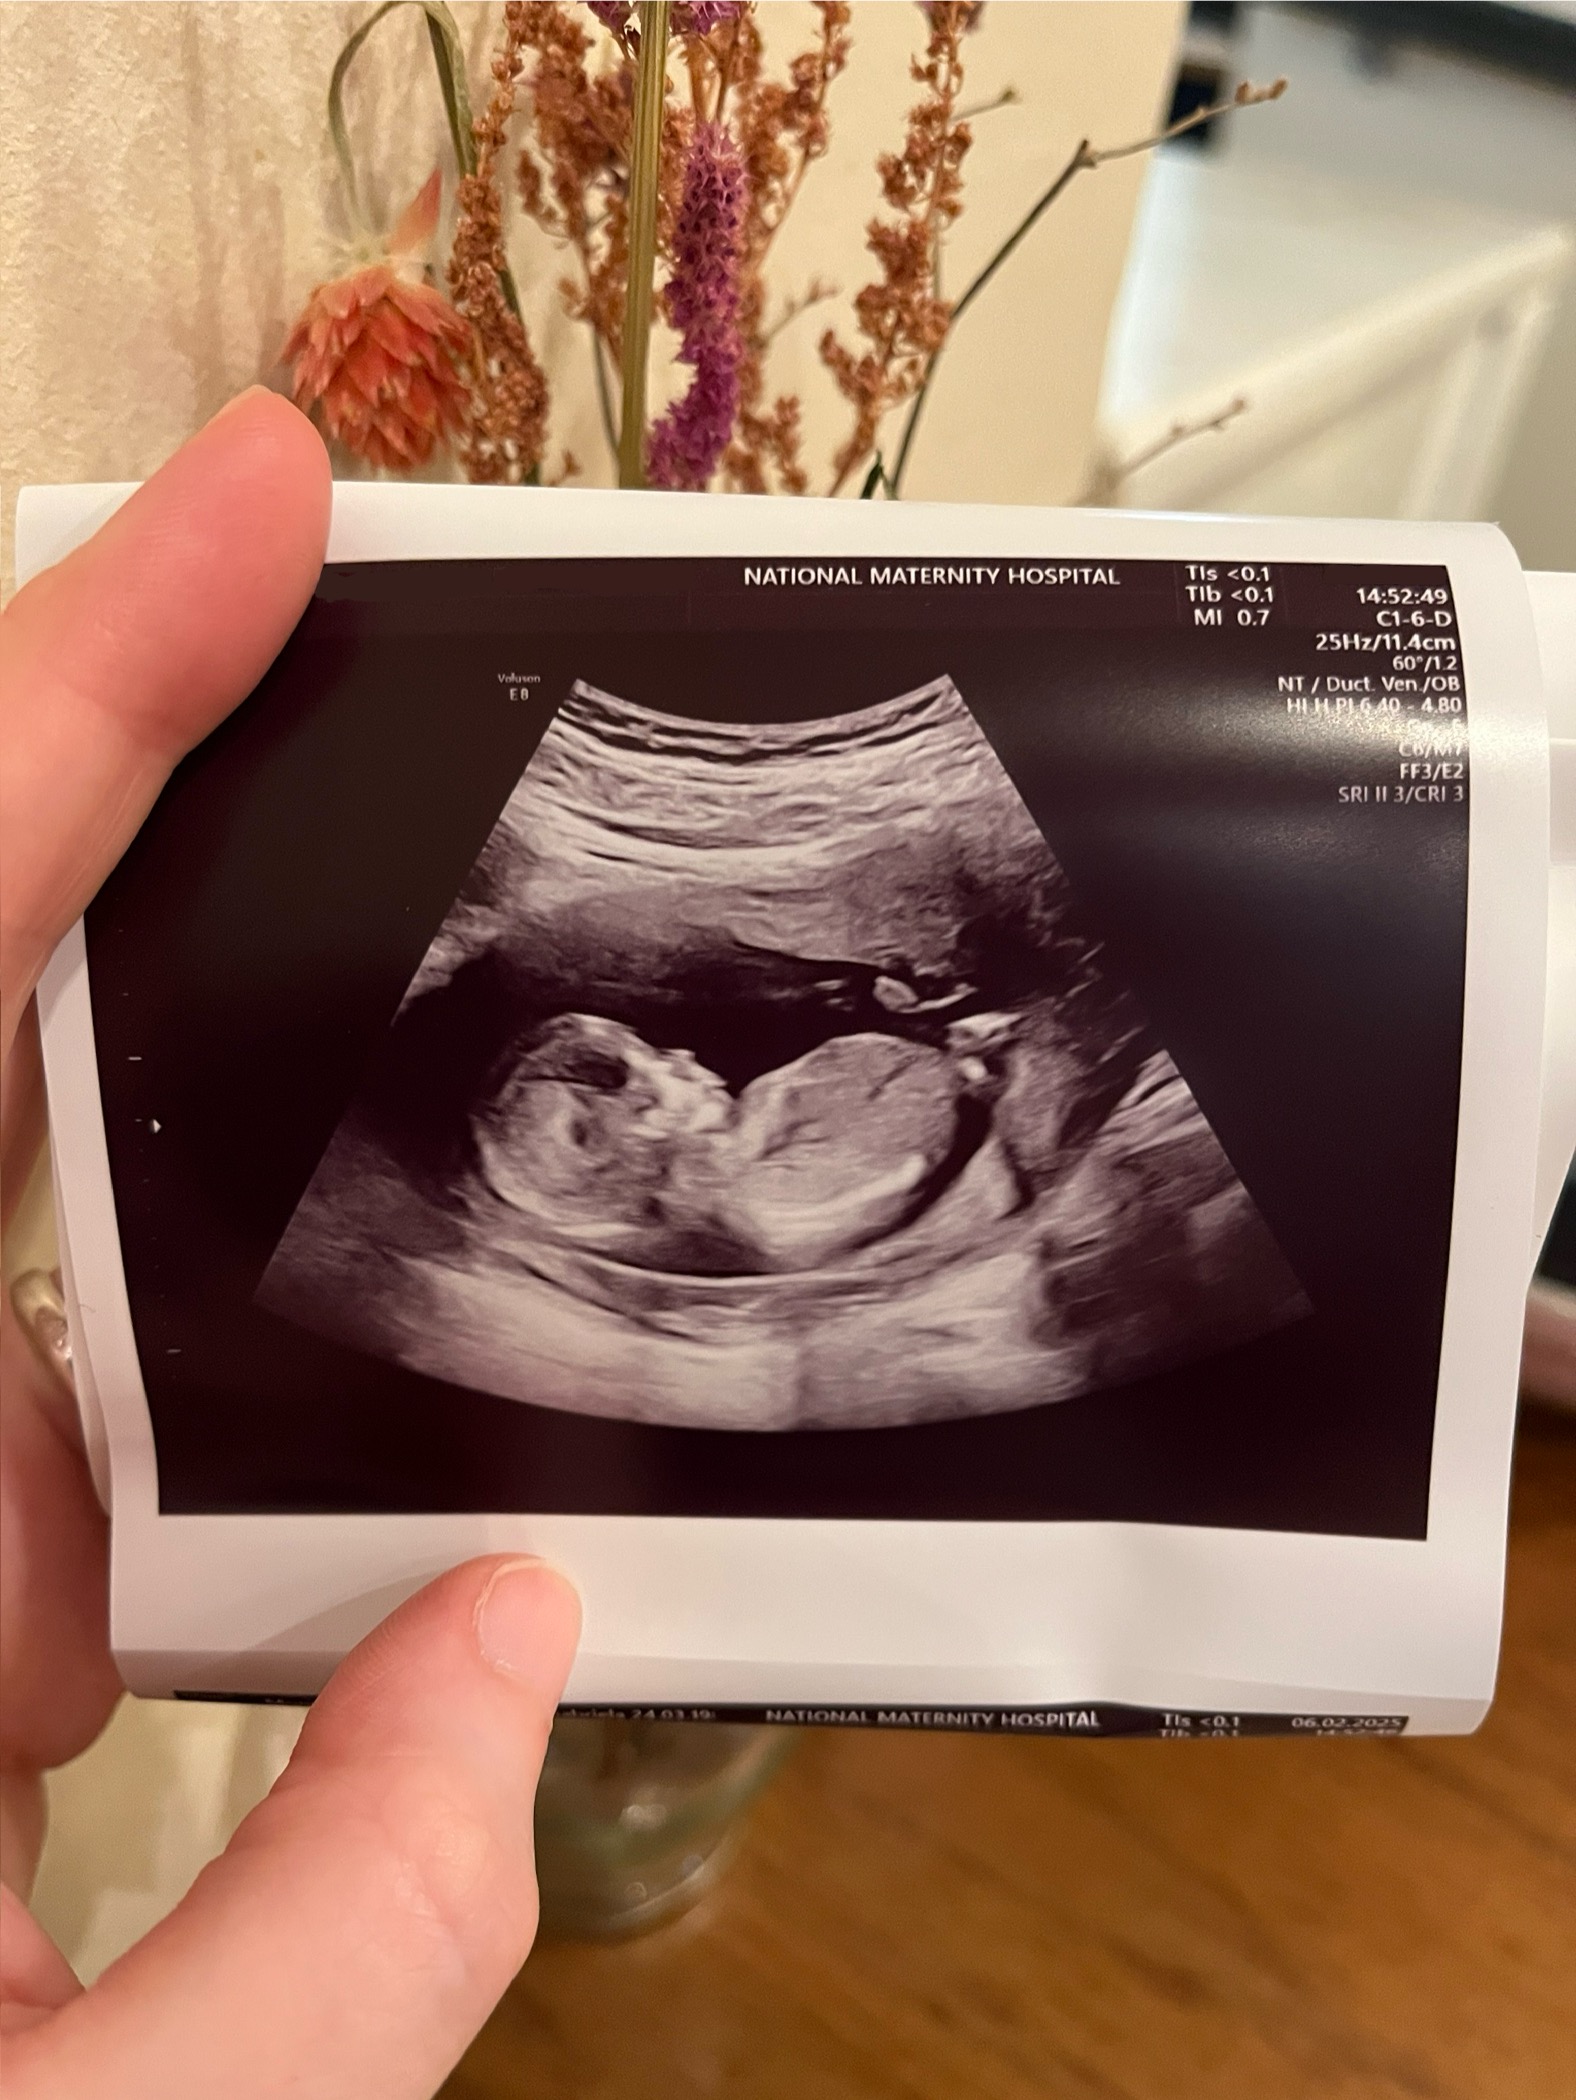

After one failed transfer, their second embryo transfer was successful, and their baby is due in just a few weeks.

D and J have kindly allowed us to share their journey under their initials and have even shared a special ultrasound image. We’re incredibly grateful for their openness—and their hope that by telling their story, other couples might feel more informed, inspired, and supported as they begin their own.